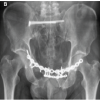

Radiographs of the knee revealed increased medial joint opening with respect to the normal knee joint. (Fig. 1) Local examination of right knee showed increased medial joint space opening with positive valgus stress and posterior sag signs, suggestive of MCL and PCL injuries (Fig. 2).

Figure 1: Pre-operative X-ray of right knee showing increased medial joint space opening.